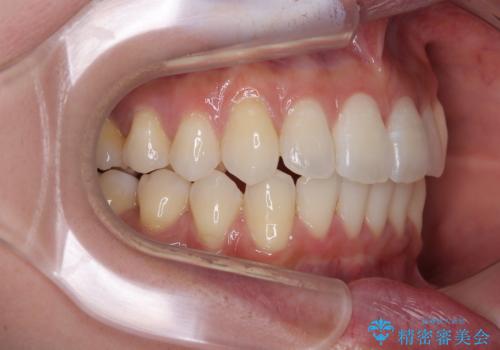

横顔は元々突出した印象ではなかったのですが、上顎前歯の角度が改善したことで、唇の閉じにくさが改善されました。